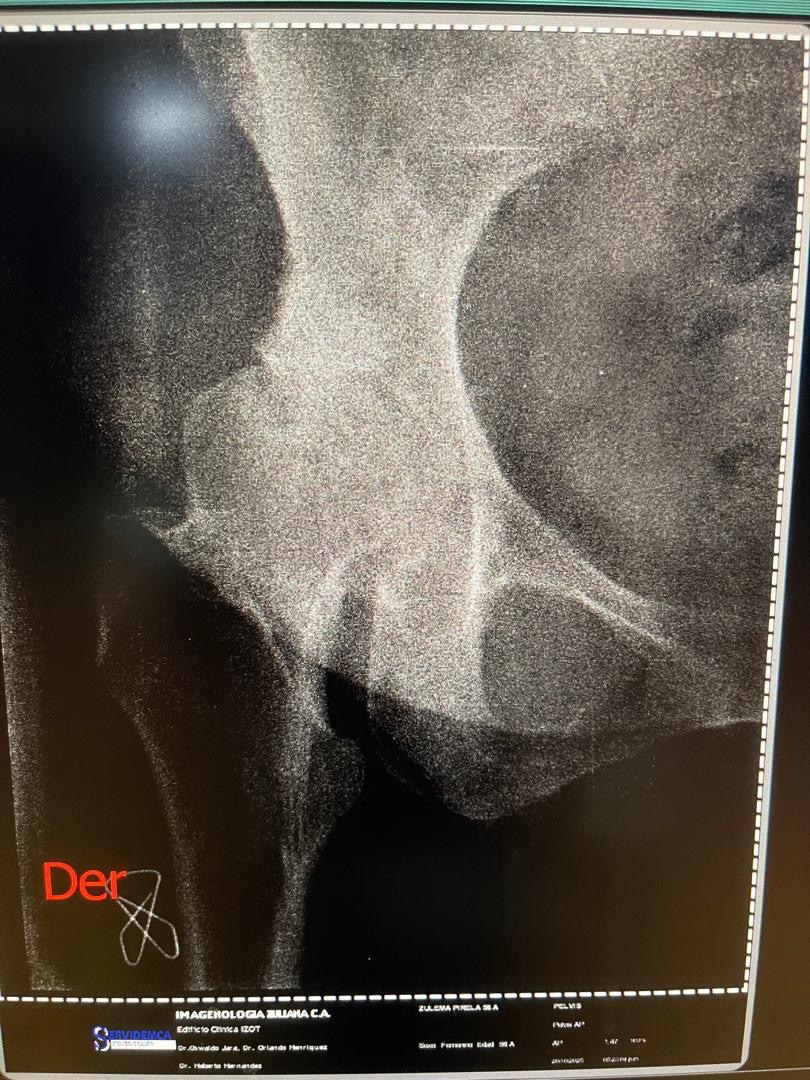

Después de más de tres años de dolor constante en la cadera, y tras consultar con distintos especialistas, finalmente hemos obtenido un diagnóstico definitivo: necrosis avascular de cadera derecha.

Este diagnóstico significa que parte del hueso de su cadera ha perdido irrigación sanguínea, lo que provoca la muerte del tejido óseo y un deterioro progresivo y muy doloroso en su movilidad.

Todos los presupuestos y diagnósticos están debidamente respaldados con informes médicos, presupuestos oficiales y estudios de imagen.